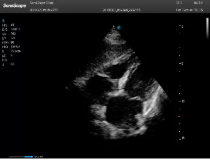

不同的探头对应于不同的临床领域,不同的探头频率也应用于不同的人体组织。超声波在人体中的衰减与探头频率有关,探头频率越高,穿透力越弱,分辨率越高,而探头频率越低,穿透力越强,分辨率越低。因此在检查浅表器官时应选用高频探头,而检查深部脏器时则选用穿透性强的低频探头。

Mark点:每一把探头都有一个mark点,是用于定位方向, mark点一侧始终对应着图像S点(图像箭头标识)一侧。